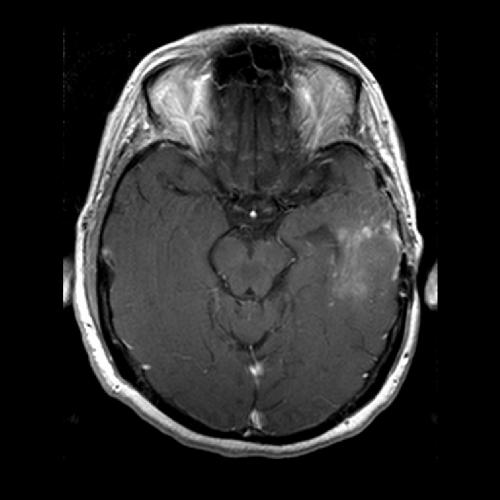

Técnicas de RM avanzada desarrollados en los últimos años pueden determinar factores como el tamaño, el radio y la capacidad de los vasos sanguíneos. VAI combina información de dos tipos de tecnologías avanzadas de imágenes de RM y los analiza de una manera que se distingue entre las pequeñas arterias, venas y capilares, determina el radio de estos vasos y muestra cuánto se entrega de oxígeno a los tejidos. El equipo del MGH VAI utiliza para analizar datos de RM adquiridas en un ensayo clínico de fase 2 – dirigido por Tracy Batchelor, MD, director del Centro de Pappas Neuro-Oncología en el MGH y coautor del trabajo actual – de la droga anti-angiogénesis cediranib en pacientes con glioblastoma recurrente. Las imágenes habían sido tomadas antes del tratamiento se inició y luego 1, 28, 56, y 112 días después de que se inició.

En algunos pacientes, VAI identifica los cambios que reflejan la normalización vascular dentro de los tumores – en particular los cambios en la forma de los vasos sanguíneos – después de 28 días de tratamiento cediranib ya veces ya en el día siguiente. De los 30 pacientes cuyos datos fueron analizados, VAI indicó que 10 fueron verdaderos respondedores a cediranib, mientras que los 12 que tenía un empeoramiento de la enfermedad se caracterizó como no respondedores.